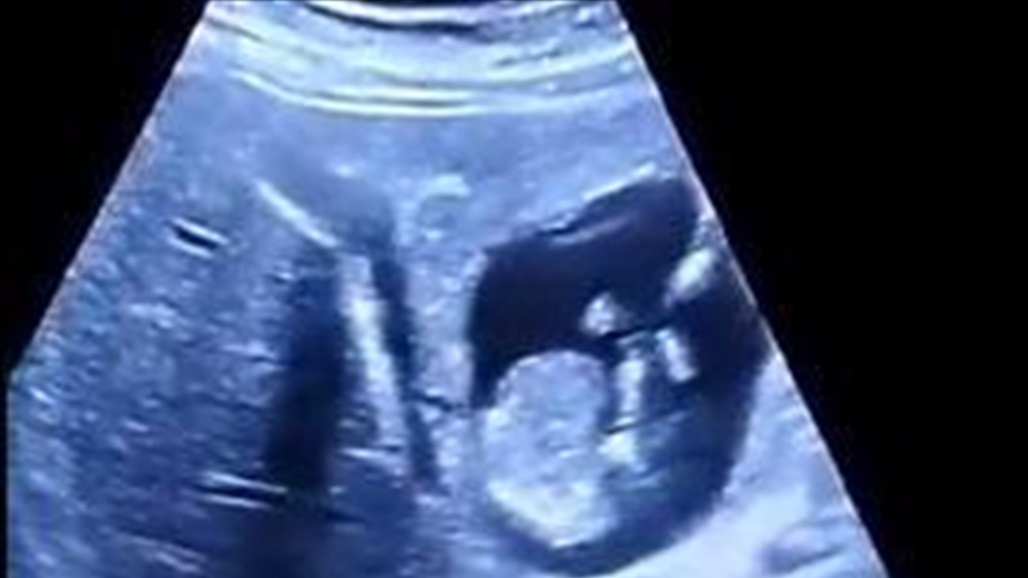

أخبر الطبيب الكندي مايكل نارفي، الذي يعمل في معهد الأبحاث بجامعة مانيتوبا، في حسابه على تيك توك عن حالة غير عادية من الحمل خارج الرحم.

وفقا للطبيب، بدأ جنين المرأة البالغة من العمر 33 عاما في التطور في الكبد، وقال إن هذه هي الحالة الأولى التي تصادفه من هذا النوع.

علق نارفي على نتائج صور الموجات فوق الصوتية للمريضة: "اعتقدت أنني رأيت كل شيء بوضوح تام".

وفقا للأخصائي، فإن الممارسة المعتادة في حالات الحمل خارج الرحم هي ظهور جنين في تجويف البطن، ولكن ممكن أن تكون هذه الحالة الأولى المسجلة لحمل في الكبد.